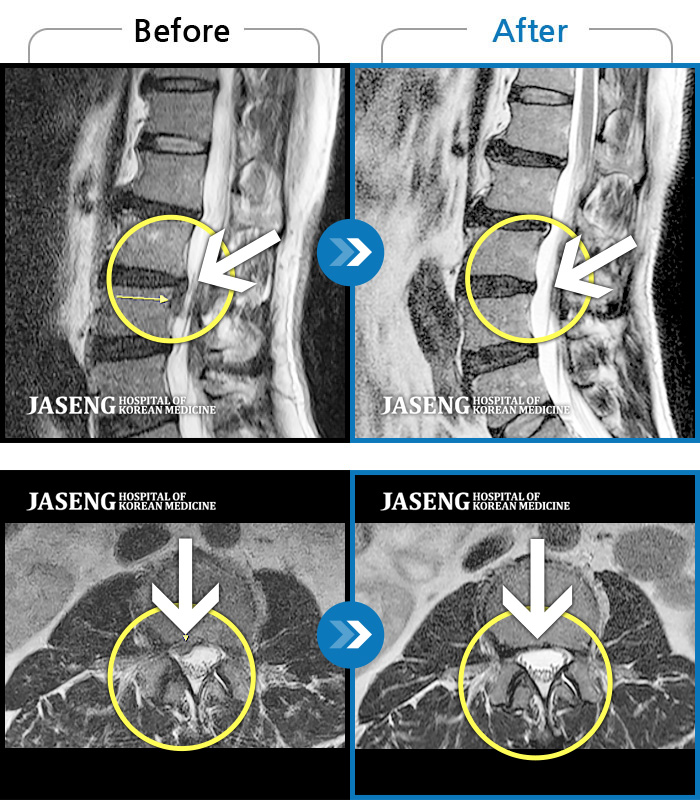

MRI을 찍어보니 3년전보다 증상은 더 심해져 있더군요